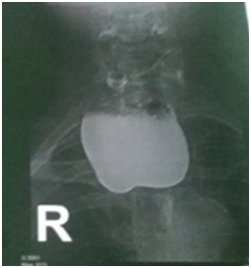

All six patients were symptomatic Four of patients were male. Age of patients was 65 to 80years. Four of patients came with dysphasia aspiration, halitosis, and malnutrition and regurgitation, one of this patient present three period with aspiration pneumonia and hospital admission. One of patients underwent endoscopic diverticulotomy and 24 hour after this procedure present with odynophagia, fever and neck subcutaneous emphysema With B-swallow perforation of diverticula was demonstrated, this patient underwent neck exploration and diverticulectomy and drainage. Diagnostic tools of five cases was B-swallow and esophagoscopy (Figures 1-5). One came with food marital retention and pain and neck mass tender mass. One patients referred with erithem, redness and criptation of neck with diagnosis of diverticulitis (Figures 6 & 7). Two cases underwent flexible endoscopic diverticulotomy, one failed and another ones complicated with perforation. The most common surgical approaches was diverticulectomy and myotomy in four patients (Figures 8 & 9). Food debris was present in one patient (Figure 10). Two of patients underwent diverticulectomy without myotomy. Complication and mortalities were zero. In two years flow-up, Outcome was good.

Figure 4 Show swallow of a 80 year old man with huge Zenker's diverticulum.